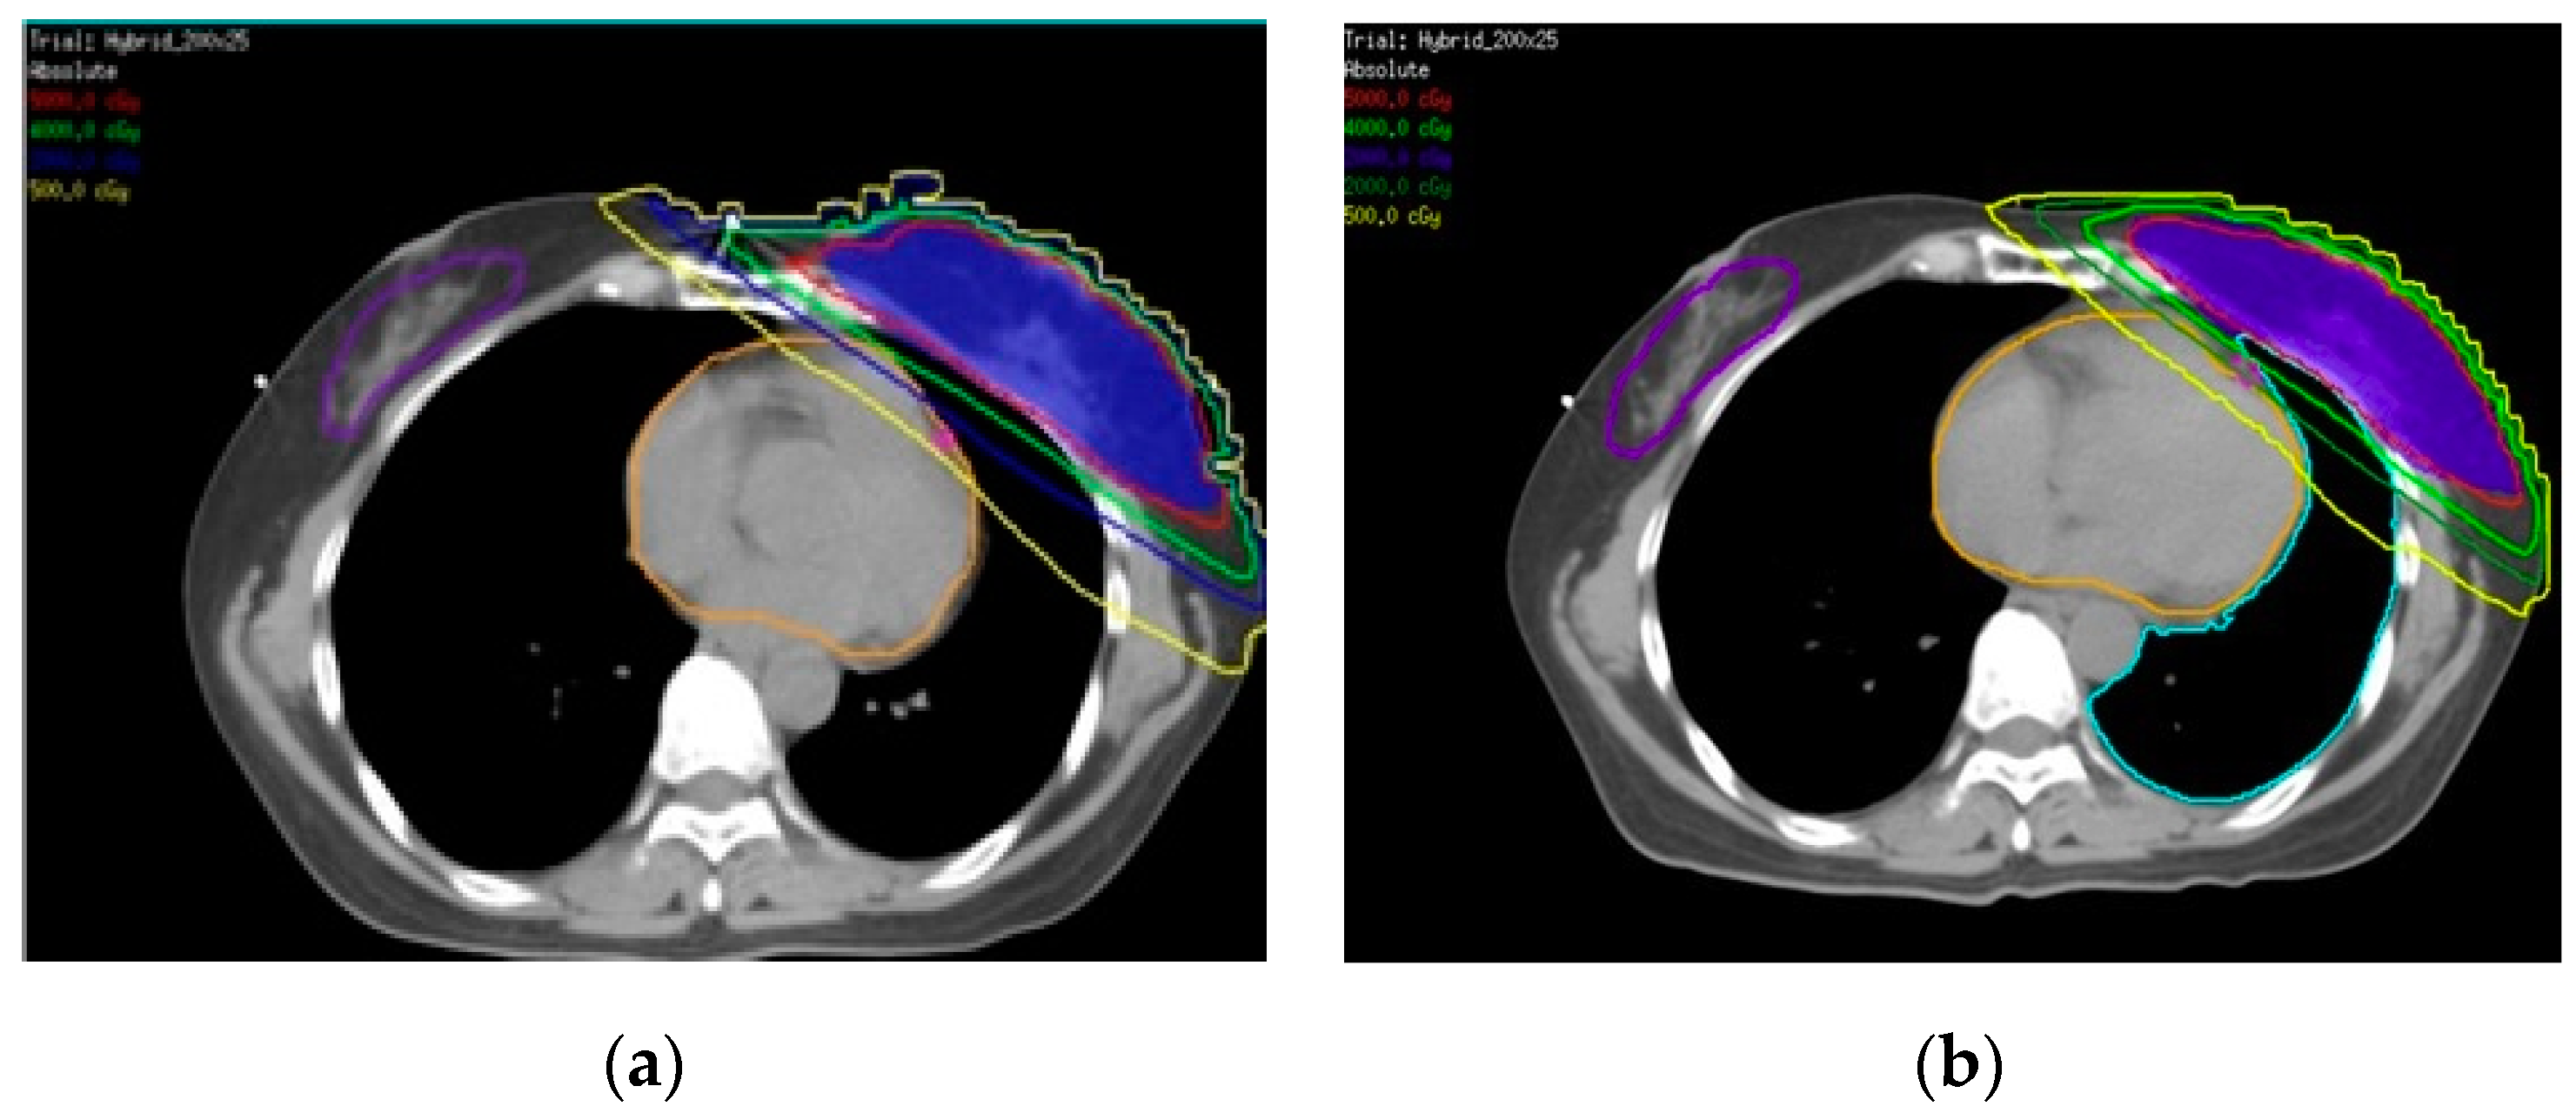

2.2.2. Patient

2.3. Surface Dose Measurement